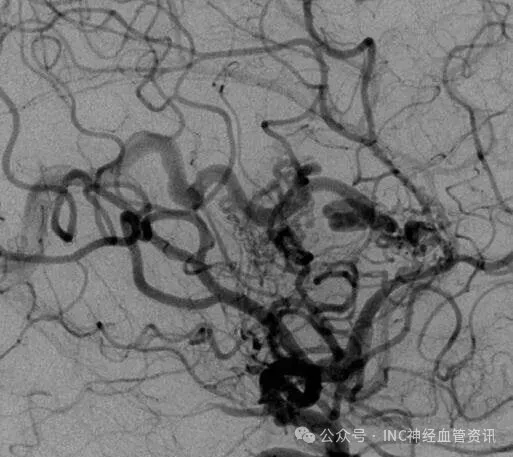

某个清晨,23岁的Anna突发剧烈头痛,紧急送医后检查显示脑室内出血,病因为透明隔区动静脉畸形。此为罕见的脑室系统病变,特征为异常血管缠结形成血管团,具有高度破裂出血风险。按照Spetzler-Martin分级系统,其病情评为5级(S2V1E0/A2B0C0),属于高风险类别。

Anna的AVM由多条动脉供血:ACA/PcaA分支、ACoA穿支和mPChA,形成复杂血管网络。首次伽马刀治疗后,血管团部分闭塞,但残留畸形血管仍构成出血威胁。

当时面临两种治疗方案:开颅手术彻底切除或创伤较小的伽马刀放射治疗。出于对开颅手术的顾虑,Anna选择了伽马刀治疗。治疗后畸形血管团虽有缩小,但未完全消失。此后四年间,她经常出现轻微头痛症状,每次发作都引发对再次出血的担忧。